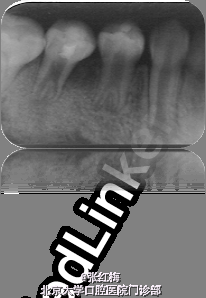

45牙合面充填体完好,边缘密合,叩痛(+),松I0,冷热测均无反应,舌侧牙根对应粘膜见1×1.2cm2 脓包扪诊有波动感,X线:发育8-9期,根中下1/3分成两根,根尖孔喇叭状,根尖周低密度影。

在牙髓再生术后1个月,3个月,5个月,9个月复查 1个月x线:45根尖周低密度影缩小,牙根继续发育。 3个月x线:45根尖周未见病变影,根周膜清晰,牙根继续发育。 5个月x线:45根尖周未见病变影,根周膜清晰,牙根继续发育。 9个月x线:45根尖周未见病变影,根周膜清晰,牙根继续发育,已近完成,髓腔缩小。 讨论:由于畸形中央尖一部分有髓角伸入,因此发现畸形中央尖应根据不同情况给予及时或相应处理。对于圆钝而无妨碍的中央尖可以不做处理。尖而长的中央尖容易折断或被磨损而露髓.可在麻醉和严格消毒下将此尖一次磨除。制备洞形,盖髓充填。还有一种方法树脂在牙尖周围加固防折,使畸形尖随牙齿一同发生生理磨耗,促使髓角形成修复性牙本质,可用于尚未建合的牙。短期内折断的畸形中央尖无牙髓根尖炎症状,且牙髓活力正常者,备洞盖髓充填。折断的畸形中央尖有牙髓炎根尖炎者,往往牙根未发育完成,需做根尖诱导形成术,或牙髓再生治疗。 牙髓坏死或者根尖炎年轻恒牙的牙髓治疗方法有:根尖诱导成形术,MTA根尖封闭技术,近年来的牙髓再生技术。 根尖诱导成形术,所用根管内充填材料是氢氧化钙及其制剂,诱导根尖周的组织在根尖部形成钙化屏障。需要多次复诊和更换根充药物,疗程较长,增加了根管再次污染的可能性,并不是所有都能形成根尖部的钙化封闭。而且根管壁仍然薄弱,增加了远期根折的风险。 MTA具有良好的生物相容性和封闭性,MTA根尖封闭技术中用其特性封闭根尖,防止充填材料在根尖部的外溢。生物相容性好,可以诱导矿化,但其完全固化需要较长时间,不易操作,抗菌效果不确定,价格昂贵。 牙髓血管再生术通过在操作中彻底有效的根管消毒,尽量保护牙髓干细胞和牙乳头间充质干细胞,并为这些干细胞的增殖和分化提供良好的环境,这些干细胞在信号分子和盖髓剂矿物三氧化物凝聚体(mineral trioxide aggregate,MTA)的诱导下,可以分化为成牙本质细胞和成牙骨质细胞等,从而在牙根继续发育中发挥着重要作用。研究表明,在坏死感染的年轻恒牙根管内进行成功的血管再生后,其根尖周炎症能愈合且牙根得以持续发育,出现根尖闭合、根管长度增加及管壁增厚等,牙髓血管再生术有可能成为治疗年轻恒牙根尖周炎的新选择。